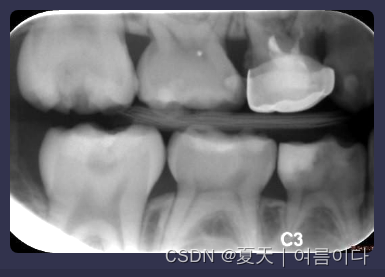

1.17.Bitewing Radiology 数据集

龋齿是一种可传播的牙齿细菌性疾病,会破坏牙齿的结构。牙医主要根据 X 光片来诊断和治疗龋齿。虽然龋齿是一种疾病过程,但该术语通常用于描述射线照相射线可透性。射线照相检查可以提高对龋齿脱矿的最早迹象的检测和诊断。自动龋病检测技术为牙科医生提供潜在的诊断数据,并帮助识别各种疾病的迹象。然而,用于放射照相龋齿诊断的准确和客观的方法却很少被探索。因此,这项挑战的目的是研究在咬翼射线照相中检测龋齿的可能的自动化方法。从 120 名患者中收集了 120 张咬翼图像。在第 1 阶段,我们将在研讨会前发布 40 张带有地面实况数据的图像作为训练数据和 40 张图像作为测试1 数据。在第 2 阶段,将发布 40 张 Test2 数据图像用于现场比赛。